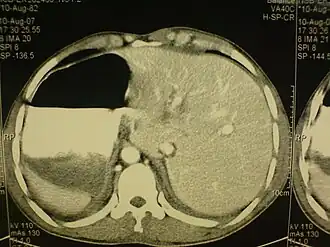

El situs inversus es una extraña anomalía congénita que puede afectar a varios órganos y tiene un carácter genético. Consiste en una alteración en la alineación de los órganos dentro del cuerpo, por la que estos se encuentran en el lado opuesto (imagen de espejo).

Generalmente va asociado a otras malformaciones, tales como poliesplenia, Síndrome de Kartagener, etc. Suele representar un serio riesgo para la vida pues en la mayoría de los casos va acompañado de malformaciones cardíacas (véase Dextrocardia). También representa un problema en cuanto a la presentación de síntomas de algunas enfermedades, por ejemplo, la apendicitis en un paciente con situs inversus presenta el dolor en el lado izquierdo, al igual que en el caso de un infarto al corazón en el cual el dolor característico se ubica en el brazo derecho.